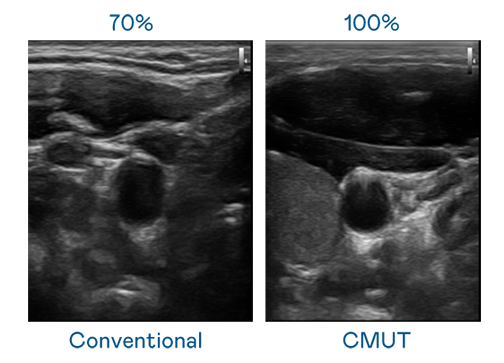

CMUT 技术是一种用电容式微机电元件来产生超音波讯号的技术。与传统 PZT 压电式技术相比,CMUT 频宽增加 30%,更宽频的超音波讯号让影像解析度大幅提升,是实现高影像品质医疗超音波扫描、促进精准医疗发展的关键技术。

超音波影像的解析度高低,首先取决于探头能发出的讯号频宽。星空体育网页版在线登录官网入口 CMUT 可提供高清晰的超音波讯号,提供高频宽、高灵敏度、影像纹理细节更高的超音波影像,协助医护人员缩短影像判读时间及利用精准的医疗影像进行诊断。